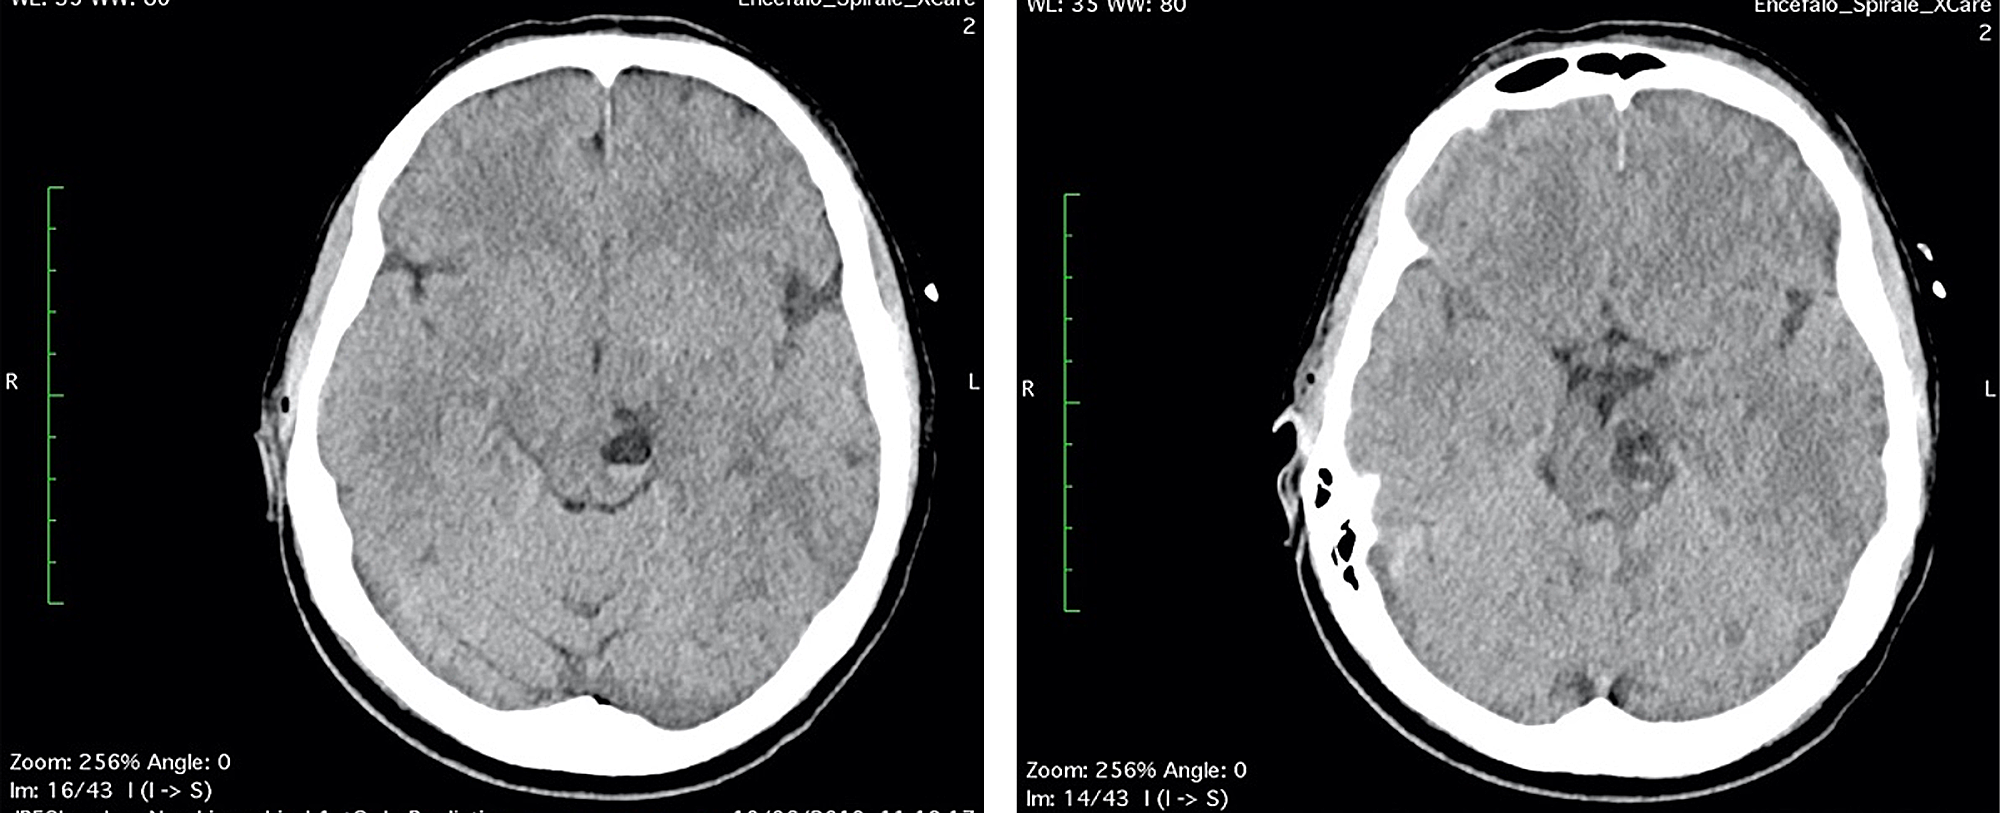

A 42-year-old woman, without previous disease, was admitted in the Emergency Room for a polytrauma during an accident car. Clinically she was conscious; she had a head trauma with hairy scalp; she complained headache and pain of the left foot; on the accident set, opiates were administered. Pressure of oxygen (PaO2) was 98%, cardiac frequency was 65 bpm, Glasgow Coma Scale was 15, and the neurological examination was negative. Laboratory tests revealed hemoglobin: 10.7 g/dL (normal range 12-16 g/dL), white blood cell: 11.71 x 109/L (normal range 4-10 x 109/L), coagulation tests in normal range, and normal platelet count. A total body CT was performed; it demonstrated, beyond the hairy scalp with large soft tissue loss in frontoparietal zone, a multiloculated cyst in the left midbrain, with eccentric hyper-density, hematic-like (Figure 1). An X-ray of the left foot showed a fracture of the first toe. In absence of neurological deficit, the patient immediately underwent surgery for the reconstruction of the scalp.

Two days after the surgery, diplopia and nausea were disappeared, vertigo persisted. The patient stayed six days more in hospital to follow the reconstruction of the scalp and to recover. Unfortunately, the patient had a reject of transplanted skin with necrosis and had to schedule a new surgery in a month later. Before discharge, a CT scan was performed in order to assess the midbrain lesion (Figure 4).

The patient was discharged and she continued the treatment for the scalp lesion and gradually recovered from vertigo. She repeated CT and MRI exams to follow the midbrain lesion up: a CT scan after one month (Figure 5) and a MRI scan after four months (Figure 6). A significant volume reduction of the midbrain lesion was observed.